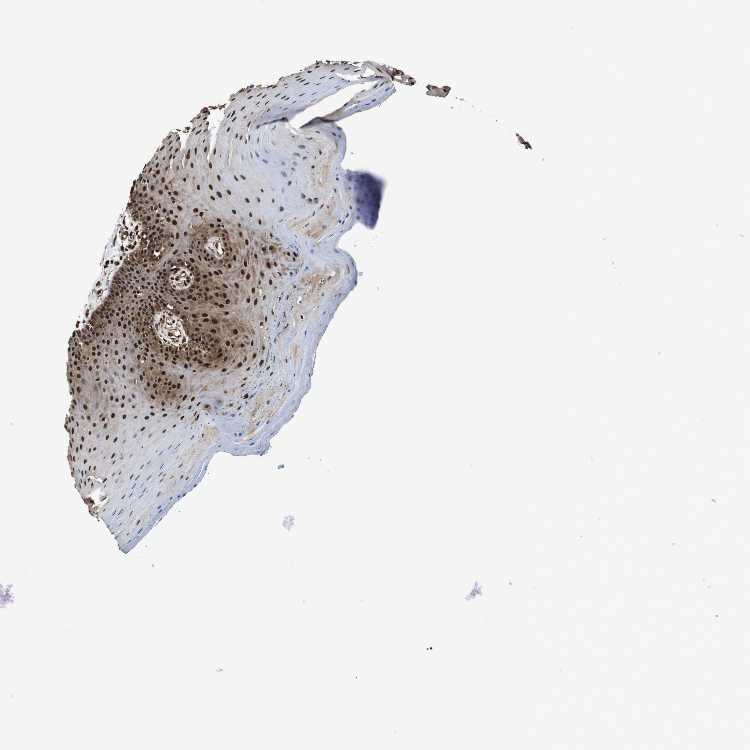

TISSUE PRIMARY DATA ORAL MUCOSA Show tissue menu

Oral mucosa

ORAL MUCOSA - Antibody stainingi

Antibody staining in the annotated cell types in the current human tissue is reported as not detected, low, medium, or high, based on conventional immunohistochemistry profiling in selected tissues. This score is based on the combination of the staining intensity and fraction of stained cells.

Each image is clickable and will lead to virtual microscopy that enables deeper exploration of all samples and also displays staining intensity scores, fraction scores and subcellular localization as well as patient and tissue information for each sample.

Antibody HPA012728Antibody HPA012814Antibody CAB005593

Squamous epithelial cells HighHighMedium